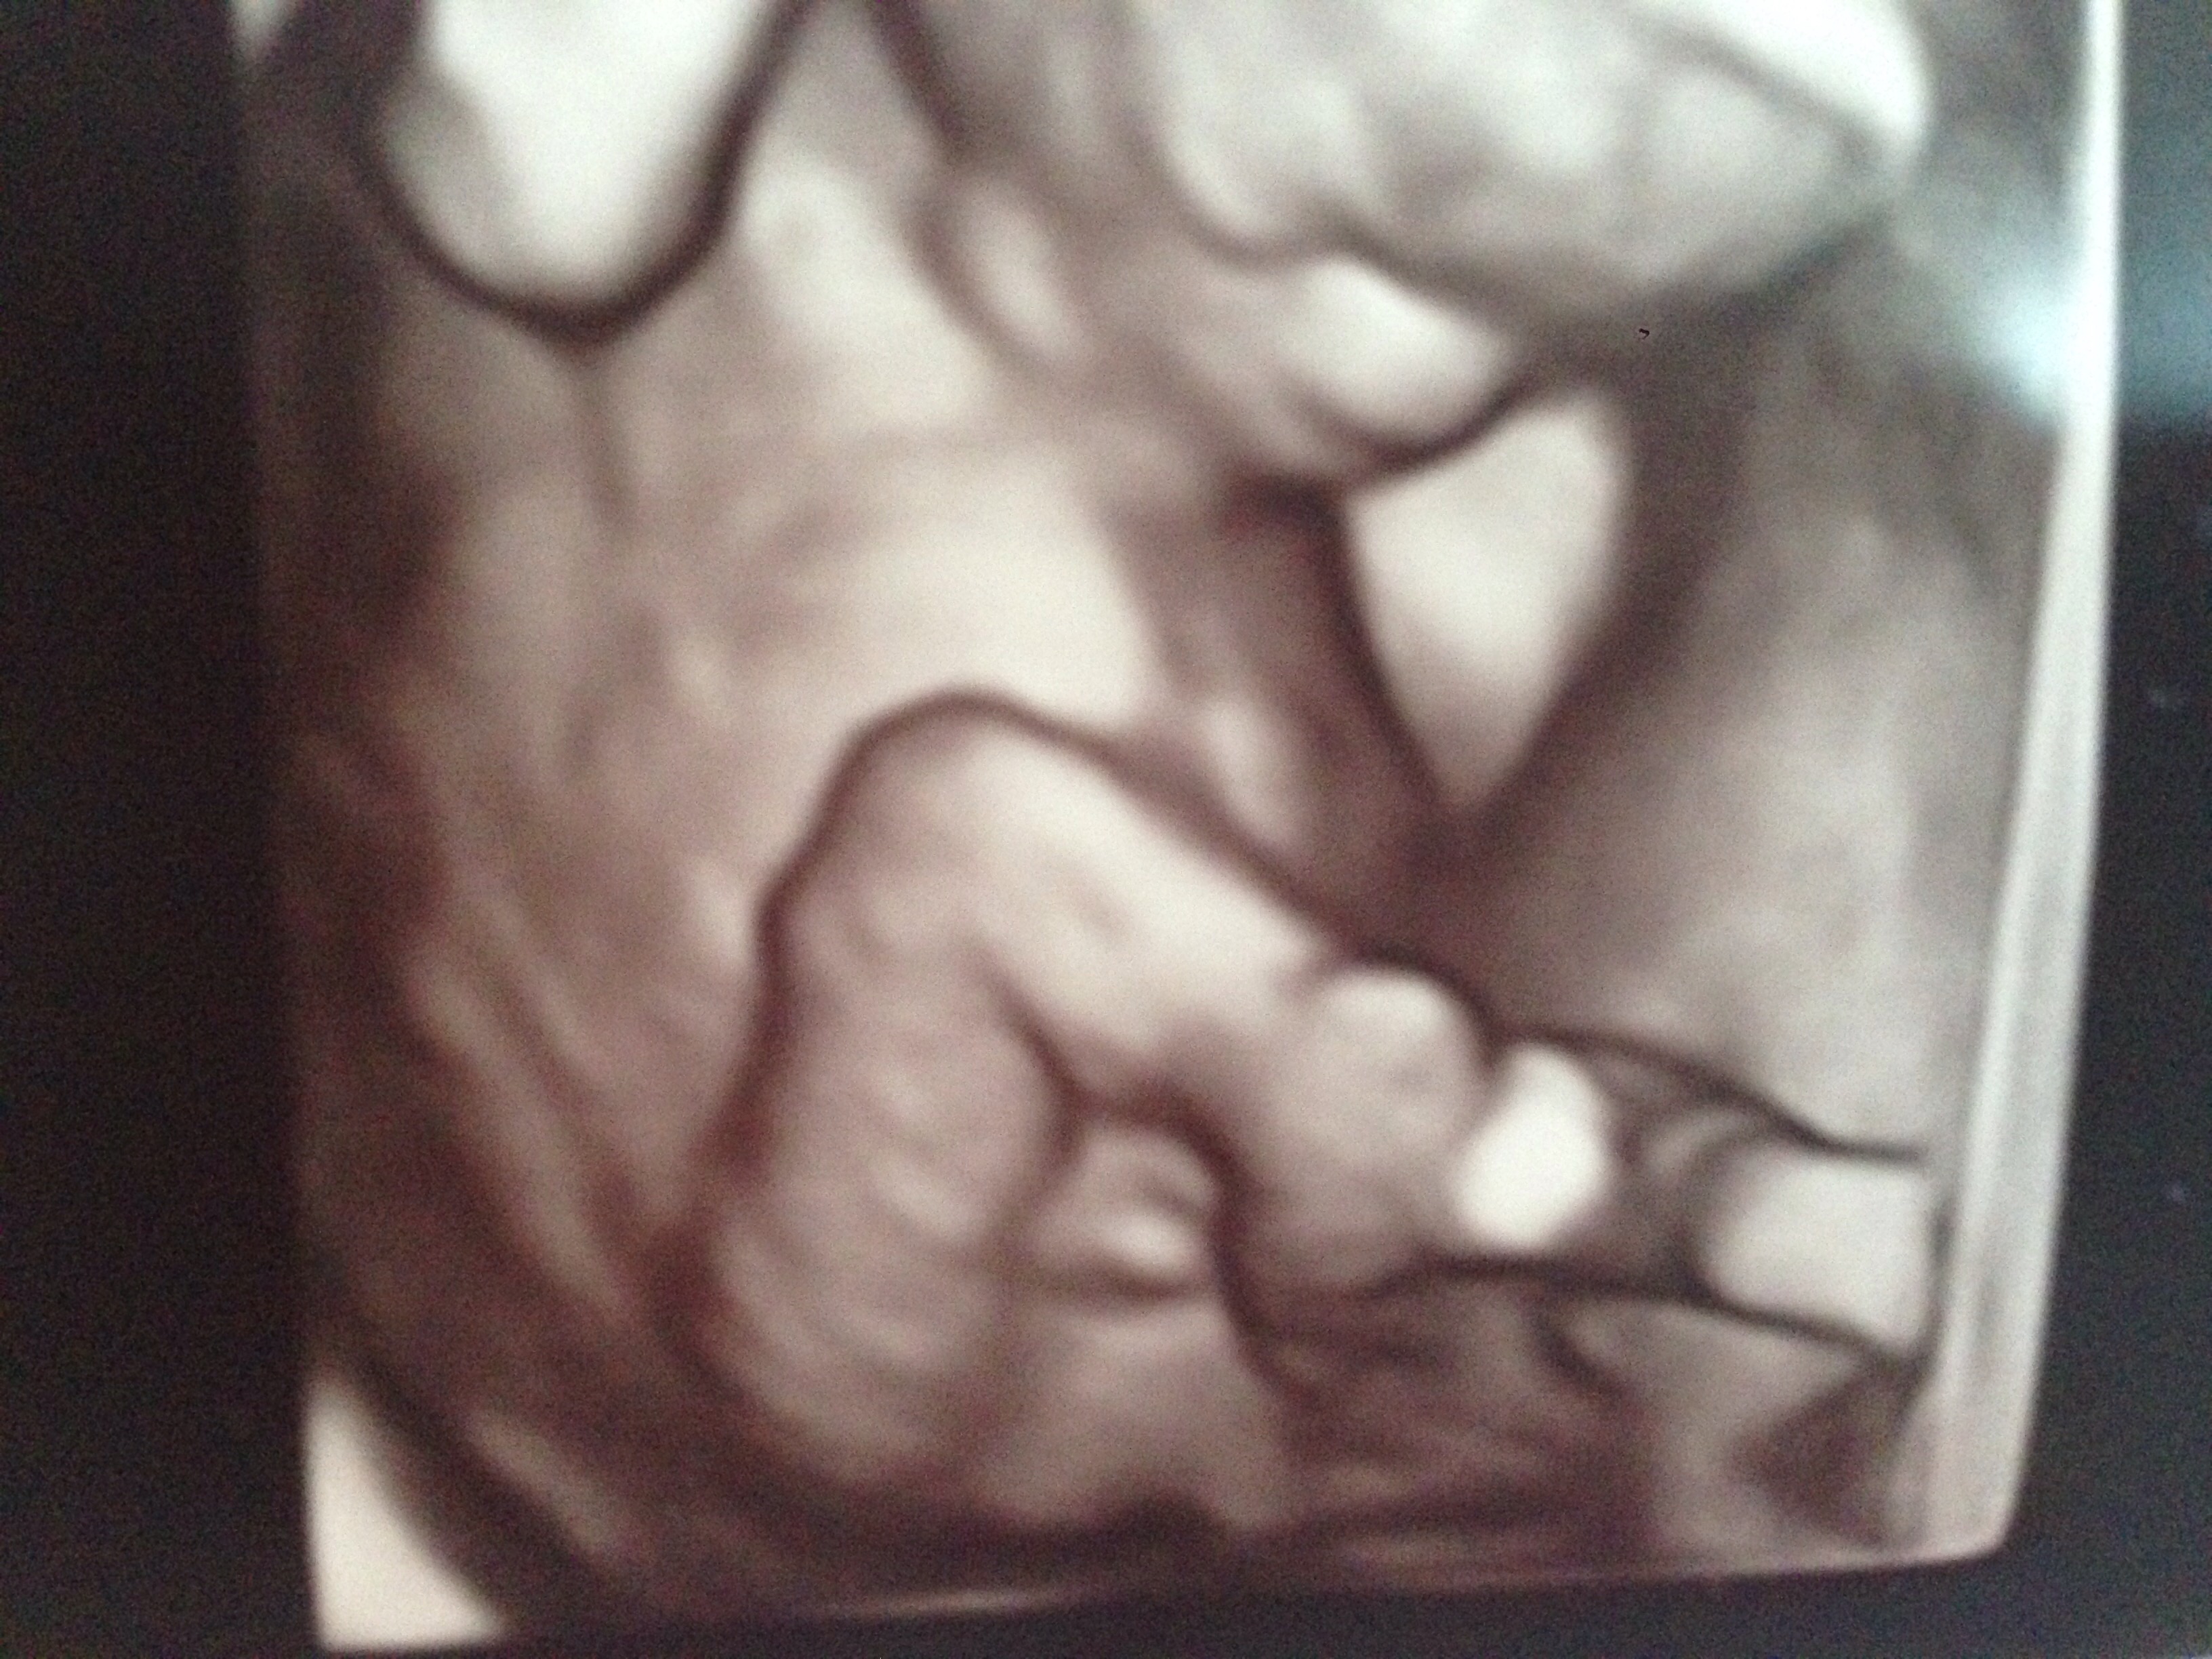

Attachment 24396Attachment 24397Attachment 24396Attachment 24397

Maybe girl?

I would guess girl too!

Which week is this? Looks boy to me!

Boy lean. How many weeks are you? Sent from my iPhone using Tapatalk